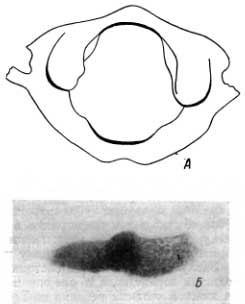

Атлант этого ребенка представлен единым костным образованием (рис. 107, А), в частности, передняя дуга и задняя дуга срослись с боковыми массами. На задней поверхности задней дуги имеется довольно глубокая выемка, свидетельствующая о том. что давность слияния обеих частей задней дуги невелика. Состояние окостенения атланта в общем соответствует тому, что обычно наблюдается у современных детей в 7—9-летнем возрасте.

Рис. 107. А — атлант ребенка-неандертальца; Б — фрагмент области синостоза седалищной и лонной костей.

Для установления костного возраста ребенка-неандертальца заслуживает внимания нижний фрагмент костного кольца вокруг запирательного отверстия, а именно место схождения лонной и седалищной костей. В этом участке уже наступил синостоз (рис. 107, Б), приблизительно за год до смерти ребенка. Структура в области синостоза характеризуется резким увеличением количества костных пластинок; это фаза физиологической костной мозоли, ошибочно рассматриваемая некоторыми рентгенологами как патологическое явление (как остеохондропатия). В действительности через эту фазу развития проходит каждый нормальный ребенок в возрасте от 7 до 9 лет.